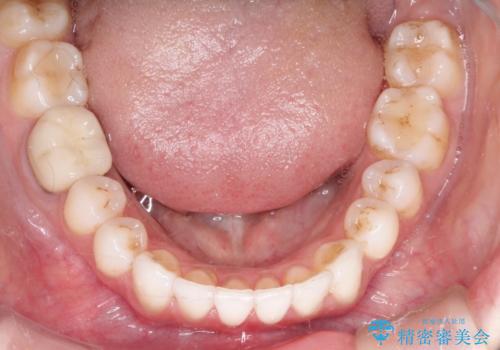

インビザラインによる非抜歯での八重歯の矯正

- 左上の八重歯と、上の歯のがたつきを主訴に来院されました。

上の奥歯を後方に移動させてスペースを作るのと、歯と歯の間をわずかに削り歯を並べる計画としました。

非常に強力的な患者様であったので、上下の正中も合わせ、ガタガタも改善することができました。